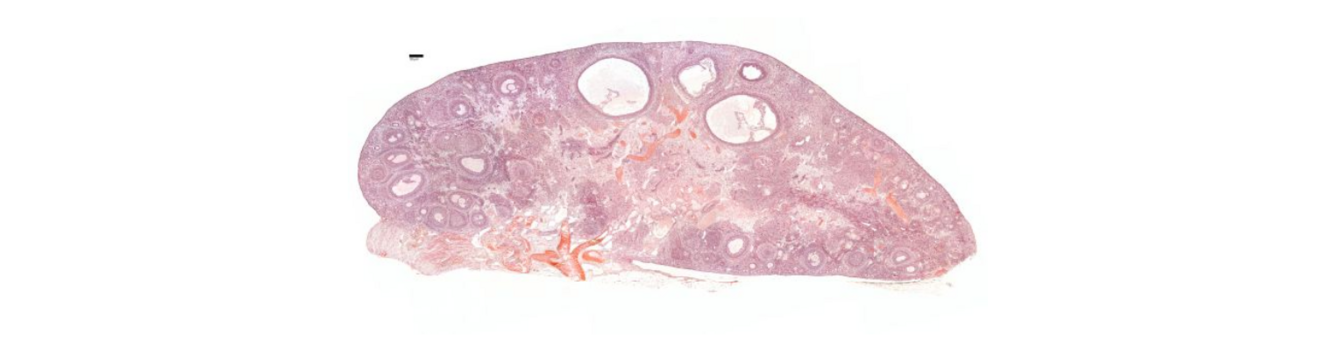

Which part of the female reproduction system is this?

A

Ovary

Q

What is the epithelium of the ovary?

Simple squamous epithelium

What is found in the cortex and medulla of the ovary?

Cortex - ovarian follicles Medulla - vascular area